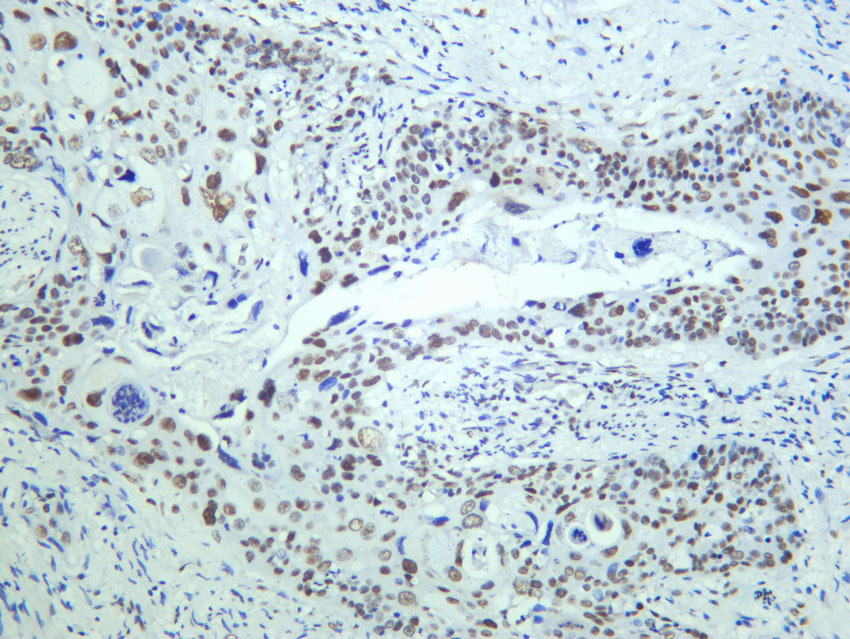

53BP1 (PT0456R) PT™ Rabbit mAb

WB, IHC, IF, ELISA, CHIP, Cut&Tag